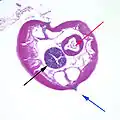

Pinworms are sometimes diagnosed incidentally by pathology: Micrograph of male pinworm in cross section, alae (blue arrow), intestine (red arrow) and testis (black arrow), H&E stain